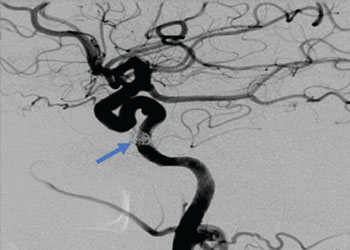

The patient is an otherwise healthy 80-year-old gentleman who presented with complaints of right frontal headaches and difficulty walking that had progressed over about three weeks. He was neurologically nonfocal. CT scan without contrast showed a large right parietal mass with midline shift and cerebral edema.